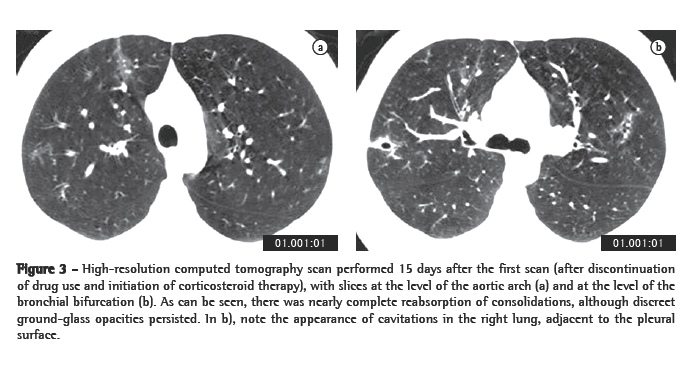

A control HRCT scan performed 15 days after the first examination (Figure 3) revealed great radiological improvement, with some persisting sparse ground-glass opacities and the appearance of some cavitations where there had been consolidations.

Regarding the HRCT scan, the only study found in the literature reports that cardiogenic edema, as well as noncardiogenic edemas such as alveolar hemorrhage, can manifest as diffuse or ­multifocal pulmonary involvement, with ground-glass ­opacities, consolidations and smooth thickening of interlobular septa, with or without pleural effusion.(9) In our patient, alterations were located in the upper and middle lung fields, as is typically seen in inhalation-related lung diseases. Lesions are ­characterized by consolidations, peribronchial nodules and ground-glass opacities. Pulmonary alterations were extensive and had disappeared almost completely by the time of the control tomography scan, performed 15 days after drug use cessation and initiation of corticosteroid therapy.

The appearance of some cavitations where there had been consolidations should be highlighted. Some authors have reported pulmonary infarction after crack use, suggesting that pulmonary infarctions result from cocaine-induced vascular spasm, with endothelial lesion and the resulting in situ thrombosis, rather than from pulmonary embolism.(1,3) The cavitations observed in our patient probably resulted from pulmonary infarction.